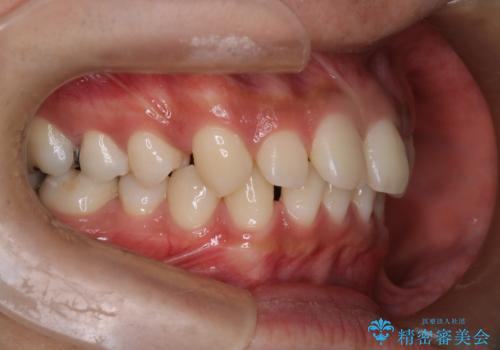

【インビザライン】空隙歯列の矯正

単純に前歯の隙間の閉鎖をしてしまうと、前歯に早期接触が生まれ、臼歯が噛まなくなってしまいます。適切な治療計画を立てることで、噛み合わせも良好な結果を得ることができました。